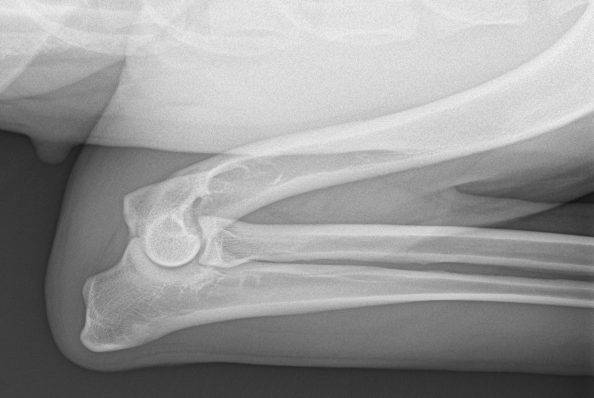

OFAの肘関節評価は両側で行い、

内側鉤状突起(FCP)

肘頭の非癒合(UAP)

離断性骨軟骨炎(OCD)

関節炎の有無(OA)

などを確認します。

特に大型犬では肘関節形成不全(ED)の発生率が高く、ブリードラインの健全性を保つうえで非常に重要です。